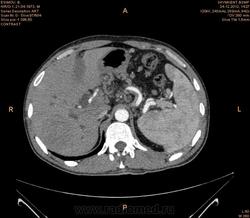

Предварительно образование головки ПЖ, и в печени. Что с ферментами?

на операций рак головки подж.железы с метастазир. печень.

инфильтрация тут нисходящей 12 перст кишки , расширенного холедох,расширенный вирсунгов проток ,нижная граница очень близко прилежит к нижней полой вене с правой почечной веной ,но четко визуализирутся передний листок фасции Героты(нельзя исключить ее инфильтрацию), инфильтрация конгломератом увеличенных лимфатических узлов ворот печени портальной вены с варикозным расширением вен, на вышележащий срезах четко определяются верхняя брыжеечная вена и артерия ,не хватает срезов для полной визуализации(помогли бы мпр),инфильтрирована восходящая ободочная кишка,конгломерат лимфат узлов за головкой поджелудочной железы в виде гиподенсивного участка вытянутой формы , ,мтс в печень,парааортальные